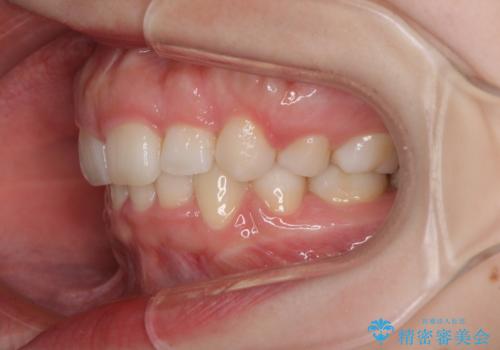

- 前歯のデコボコと上顎の前突感による口の閉じにくさを気にして来院された患者様です。

目立たない装置を希望されたので、上顎が裏側装置のハーフリンガルを選択し、上下左右の小臼歯(計4歯)を抜歯して矯正治療を行うこととしました。

期間はかかったものの、口元の張り出し感や歯のデコボコが解消され、患者様には大変満足していただけました。